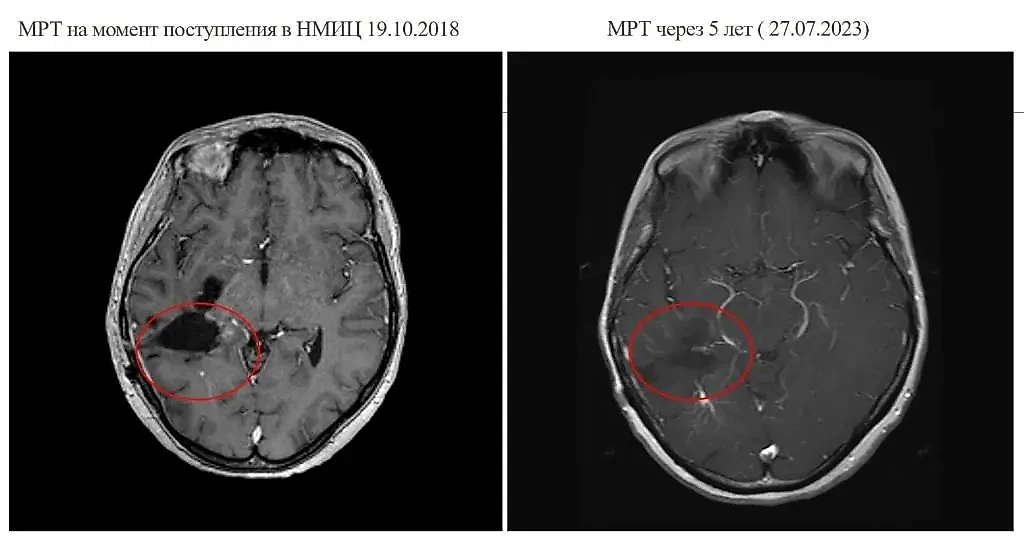

МРТ на момент поступления сибирячки с опухолью в больницу и через пять лет после лечения. Фото © VK / НМИЦ им. ак. Е.Н. Мешалкина Минздрава России

Теперь кемеровчанка живёт полной жизнью и ощущает себя полностью здоровой. Она ходит в походы, сплавляется на байдарках и радуется каждому дню. Новых очагов опухоли в головном мозге женщины врачи не зафиксировали.